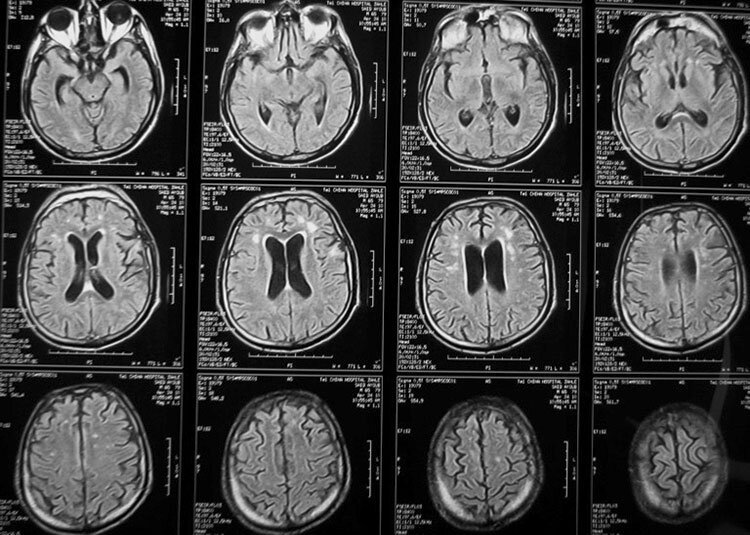

Мы ежедневно сталкиваемся с небольшим напряжением, и это нормальная часть нашей жизни, которая даже полезна для нас.Это может сделать нас более устойчивым в стрессовых ситуациях. Но когда стресс становится хроническим-например, вызванный распадом брака или отношений, потерей близкого человека или постоянным издевательствами- его необходимо устранить. Это потому, что постоянный стресс может подвергнуть ваш мозг физическим и психологическим расстройствам. Повторный стресс является причинной постоянного воспаления в организме. Это может привести к ряду проблем со здоровьем,включая диабет и сердечно-сосудистые заболевания. Мозг обычно защищен от циркулирующих молекул гематоэнцефалическим барьером. Но при повторным стрессе этот барьер ослабевает и воспалительные белки могут попасть в мозг. Гиппокамп мозга является очень важным, он отвечает за обучения и память и особенно уязвим для таких нарушений в гематоэнцифалическом барьере. Исследования показали,что стресс могут отрицательно влиять

Гиппокамп мозга является очень важным, он отвечает за обучения и память и особенно уязвим для таких нарушений в гематоэнцифалическом барьере. Исследования показали,что стресс могут отрицательно влиять на мотивацию и умственной ловкостью.

Также хронический стресс может влиять на гормоны в головном мозге, включая кортизол и релизинг-фактор кортикотропина. Высокие, длительные содержания кортизола были связаны с расстройствами настроения, а также с нарушением гиппокампа. Это может вызвать много физических проблем,включая нерегулярные менструальные циклы.